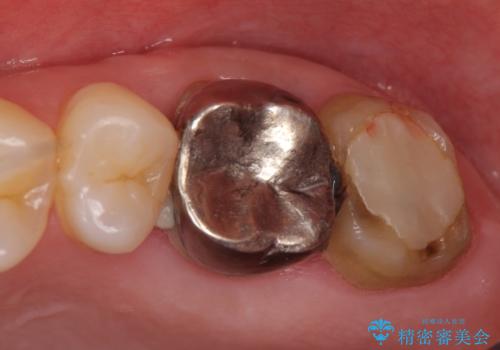

- 他院にて治療した左上奥歯の疼くような痛みが引かないため当院にいらっしゃった方の症例です。

検査の結果左上6に打診痛、根尖部圧痛、根尖病変を認めたため、再根管治療を行ったところ症状が緩解したため、オールセラミッククラウンによる補綴を行いました。

左上7は治療を希望されなかったため、オールセラミッククラウンによる補綴のみを行いました。